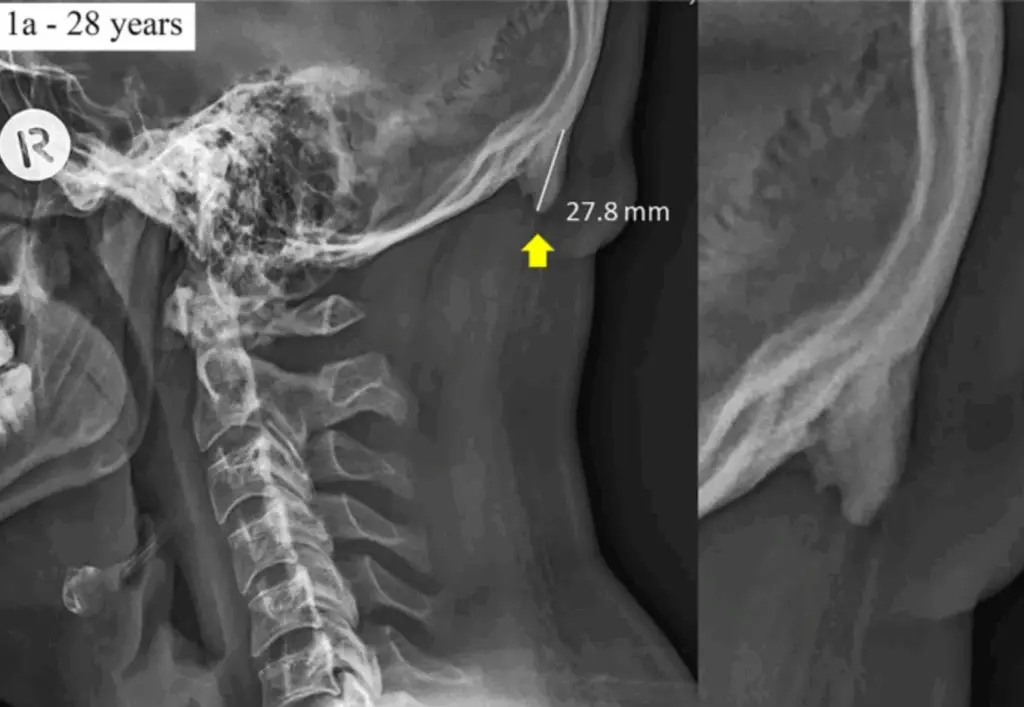

Turns out those bony bumps at the back of young people’s skulls aren’t growing from good vibes and TikTok dances. They’re growing because kids, and let’s be honest, adults too, are glued to their phones with the posture of a cooked shrimp. This 2018 study found that young guys, especially, are sprouting these skull spurs (called EEOPs) thanks to years of terrible posture and too much screen time. It’s not age or genetics, it’s tech neck. So maybe it’s time we stop handing toddlers tablets and start teaching people how to sit like humans again. Awareness of how forward your head sits is the key to making any lasting postural change. If your brain knows where you are in space (proprioception), you can correct your posture. This is where a chiropractic adjustment comes in handy.